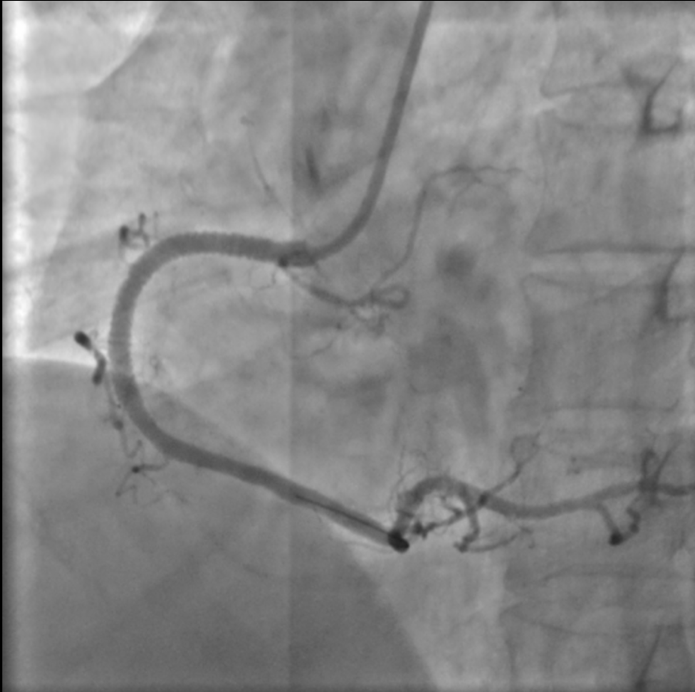

植入支架之后的右冠状动脉。

一场与时间的赛跑随即展开,泰康同济胸痛中心立即启动急性心肌梗死救治绿色通道,急诊冠状动脉造影显示郑先生右冠状动脉完全闭塞。从进入医院大门到手术器械成功开通堵塞血管仅用时51分钟,远低于国际公认的90分钟黄金标准。术后郑先生胸痛症状迅速缓解,生命体征逐渐平稳,目前已转入普通病房观察。